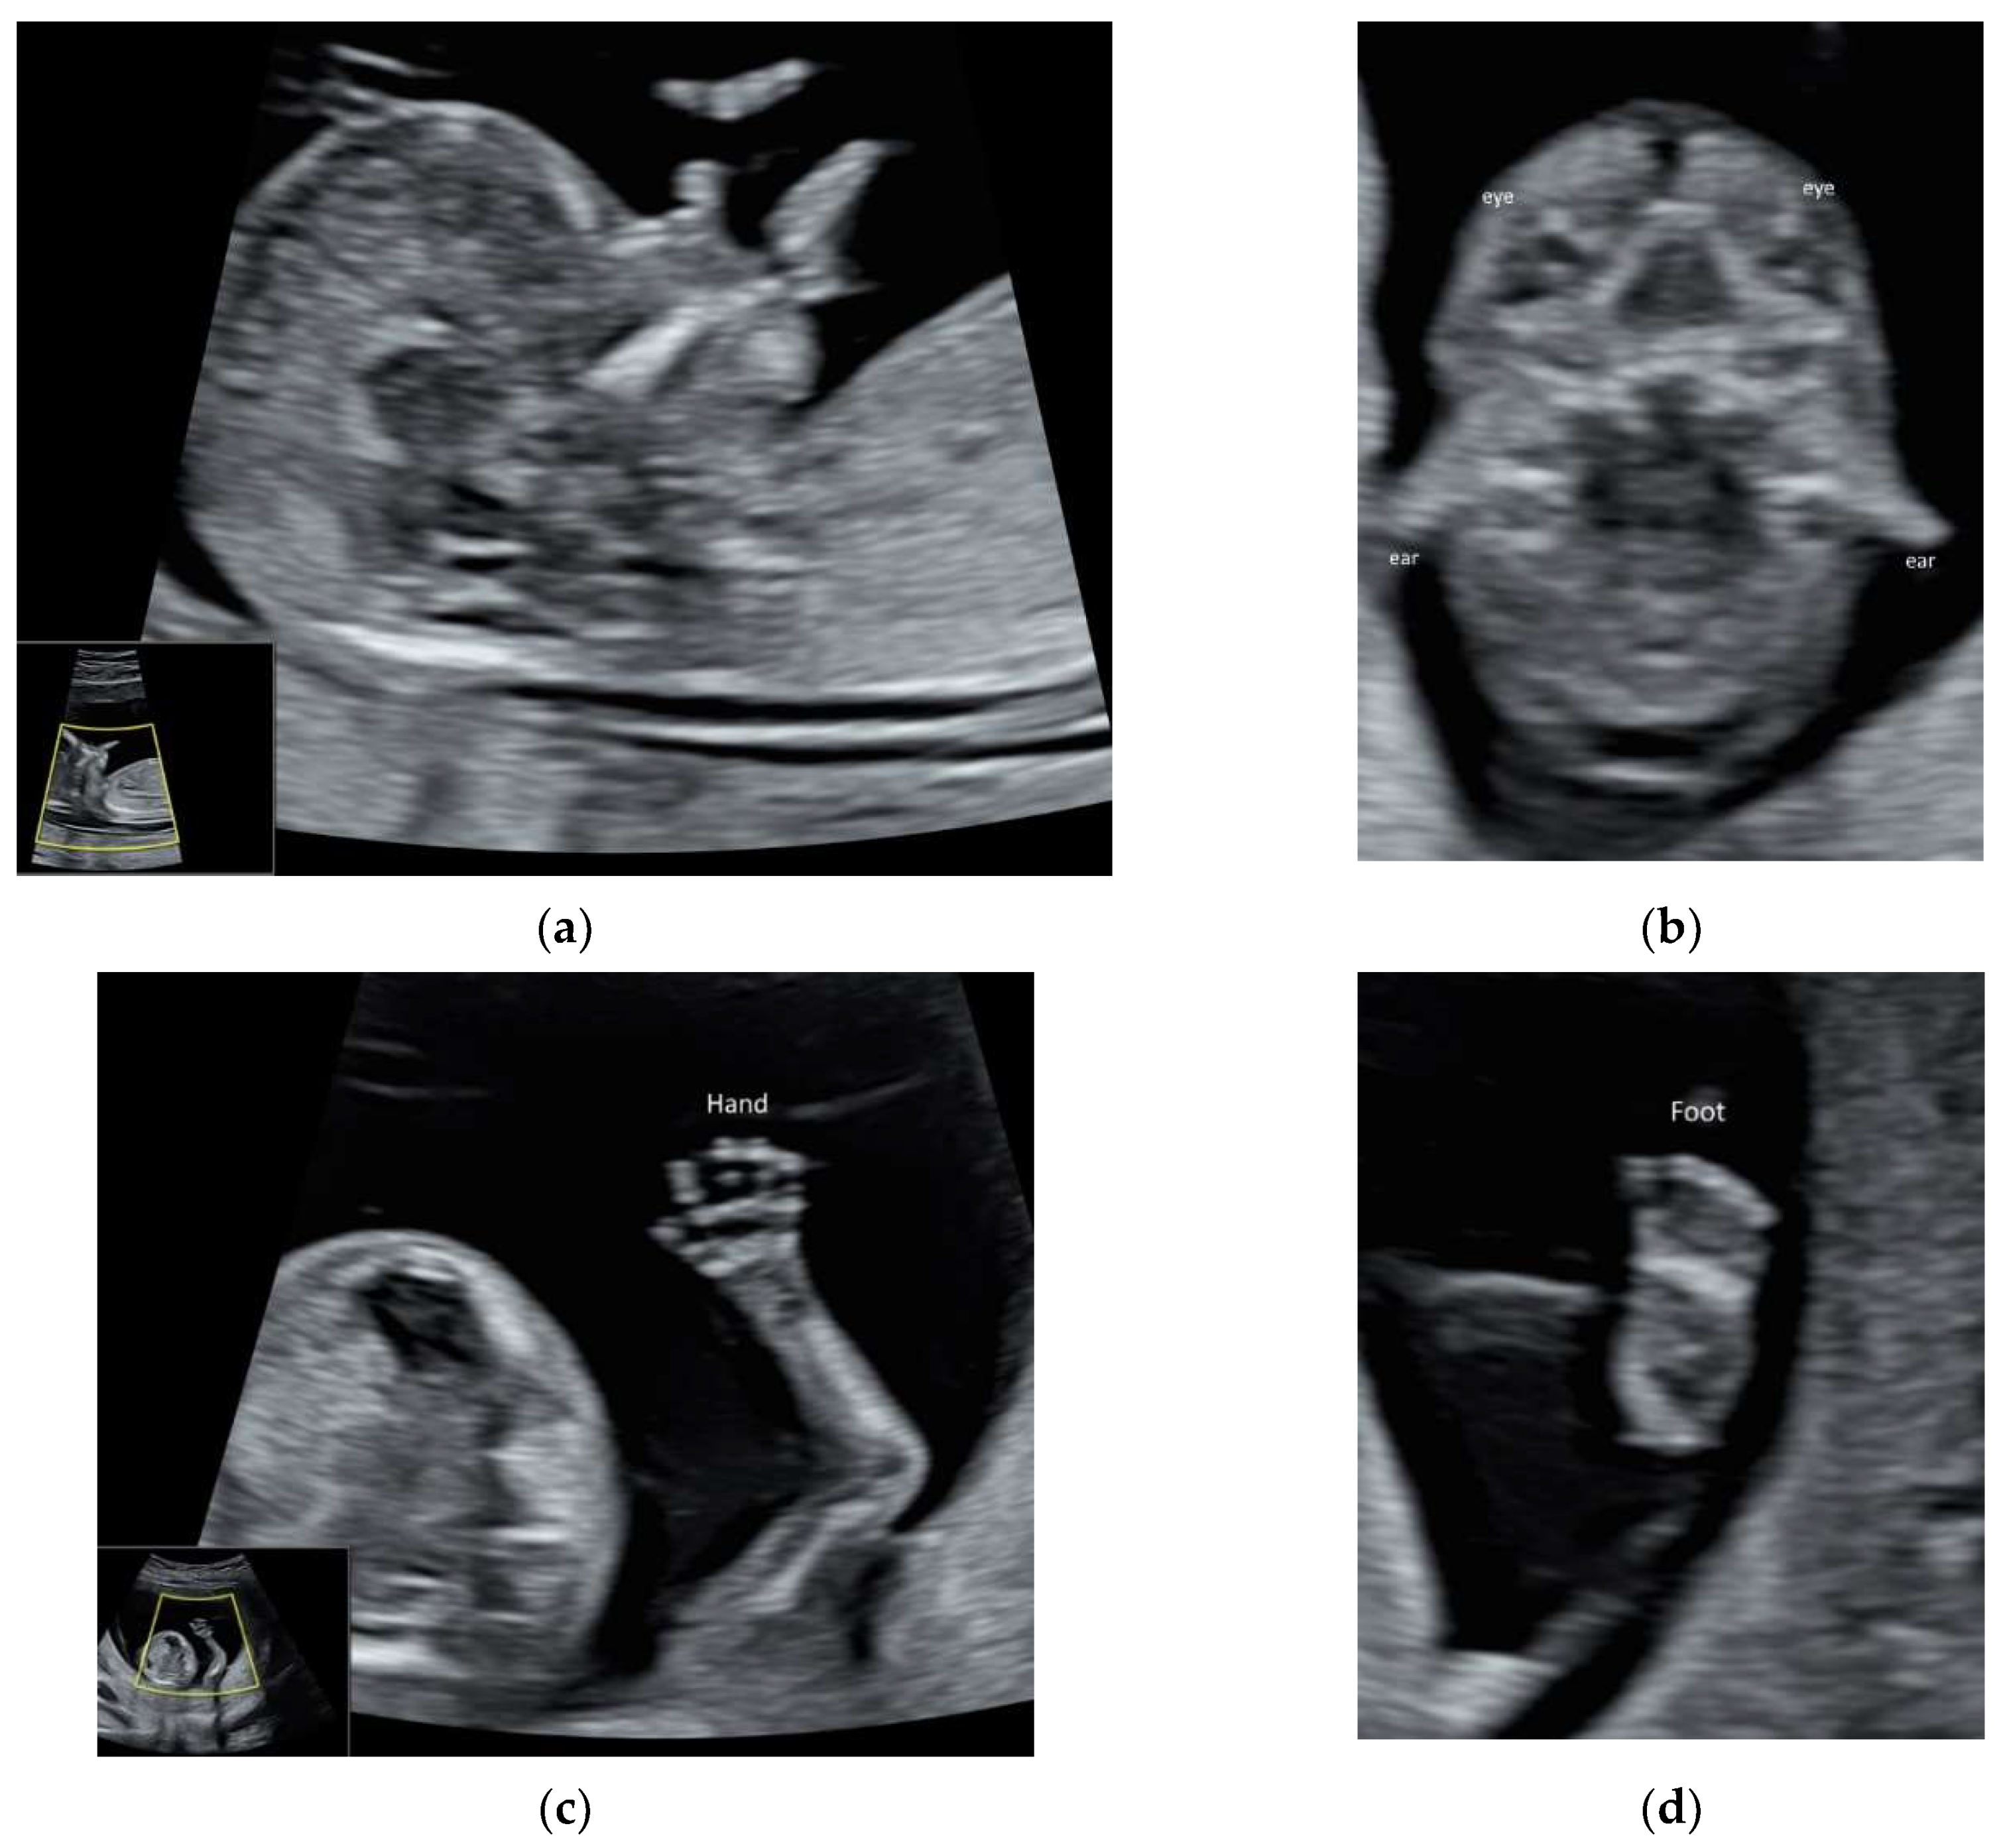

ISUOG and recently, AIUM published the practice guidelines on first-trimester fetal ultrasound scan [24,25]. High-resolution ultrasonography allows the early assessment of fetal anatomy [11] (Figure 5a–d, Video S5a,b) and fetal malformations [12]. Fetal heart can be examined in the late first trimester [26], particularly with the use of color Doppler (Video S5c,d). ISUOG recommends using high-frequency (6–12 MHz) transvaginal ultrasound to examine fetal brain, especially if the focus is in the posterior fossa and the maternal abdominal wall is thick [5].

Figure 5.

High-resolution ultrasonography of the fetus at 13 weeks’ gestation: (a) mid-sagittal view showing head, neck, and facial profile, (b) coronal view showing both eyes and ears, (c) the hand with five fingers, and (d) foot.